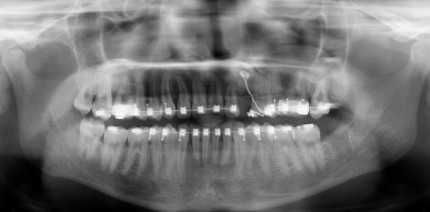

Der Patient stellte sich erstmalig im Alter von zwölf Jahren im April 2017 vor. Er wurde nach einer Frühbehandlung mit aktiven Platten bei...

Der Patient stellte sich erstmalig im Alter von zwölf Jahren im April 2017 vor. Er wurde nach...